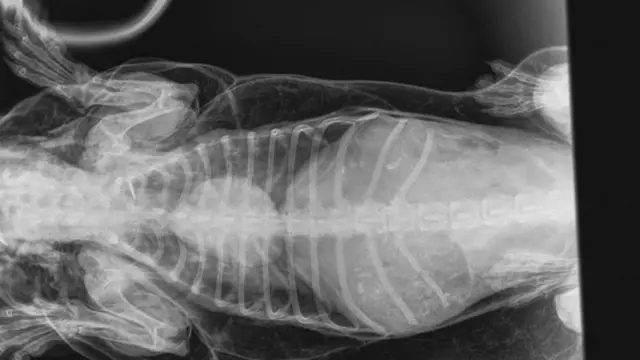

Los rayos X mostraban que cada vez que la mascota respiraba, el aire se alojaba bajo su piel y afectaba a su corazón.

Tras las pruebas, el perro fue diagnosticado con enfisema subcutáneo, una acumulación anormal de aire debajo de la piel.

La veterinaria Michelle Coward llevó adelante un procedimiento para aliviar la presión y coser un orificio en la tráquea del perro.

"No hubo lesiones externas que explicaran cómo el aire se había acumulado debajo de la piel, por lo que sospechamos que una lesión interna en las vías respiratorias podría haber permitido el ingreso del aire", añadió.

"Cada vez que respiraba, parte del aire inhalado escapaba por un agujero en la tráquea".